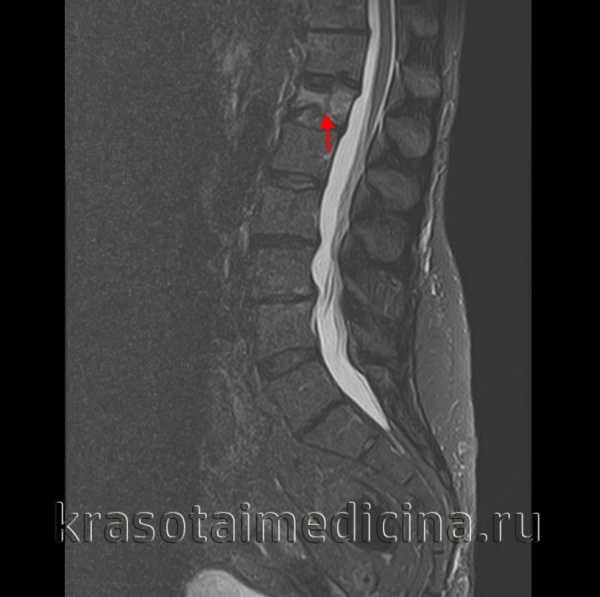

2. МРТ при гиперэкстензионном повреждении грудного и поясничного отдела позвоночника:

• T2-BИ/STIR:

о Признаки отека при мягкотканных/связочных повреждениях

о Усиление сигнала, расширение межтелового пространства свидетельствует о разрыве межпозвонкового диска

о Разрыв ППС,+ЗПС

о Усиление сигнала спинного мозга свидетельствуете его контузии:

- Нарушение целостности спинного мозга является признаком его пересечения

о MPT информативна для диагностики повреждений спинного мозга с неврологическим дефицитом и выявления невидимых рентгенологически связочных повреждений

о МРТ должна включать сагиттальные STIR/Т2-ВИ, аксиальные T2*GRE или Т2-ВИ, сагиттальные и аксиальные Т1 -ВИ

(Справа) На сагиттальном STIR МР-И отмечается патологические усиление сигнала в области передней продольной связки и нижней части тела позвонка. В области задней продольной связки и задних элементов достоверных признаков изменения сигнала не видно.